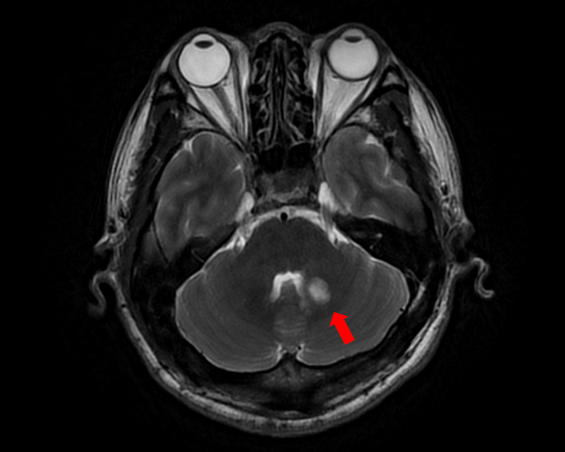

随着患者高先生颅内中脑左侧、左侧小脑两处病灶的顺利切除,国际神经外科医生集团专家已累计在苏大附四院完成了第100例高难手术。这标志着我院在神经外科国际化合作交流方面取得了里程碑式的成果,也为众多疑难脑肿瘤患者带来了新的希望。

自苏州大学附属第四医院与国际神经外科医生集团签约合作以来,Bertalanffy(巴特朗菲)教授、Froelich(福洛里希)教授等专家已多次来院开展深度医疗合作。在手术室里,国际专家与我院神经外科团队紧密配合,针对脑干、丘脑、颅底等高难度区域的复杂肿瘤,实施了包括脑干海绵状血管瘤、颅底脑膜瘤、复杂胶质瘤等一系列高风险手术。百例手术,不仅是数字的积累,更是技术与信任的双重见证。